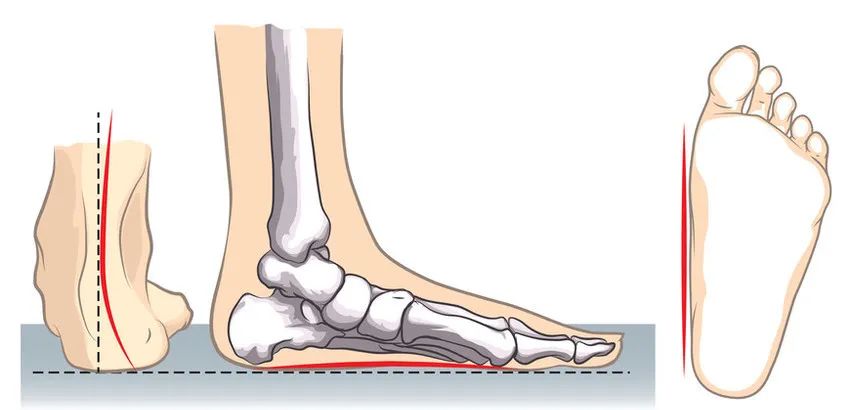

同济医生说俞光荣平足症是否需要手术治疗

扁平足和僵硬性扁平足,需要儿童骨科医师仔细鉴别检查,特别是垂直距骨